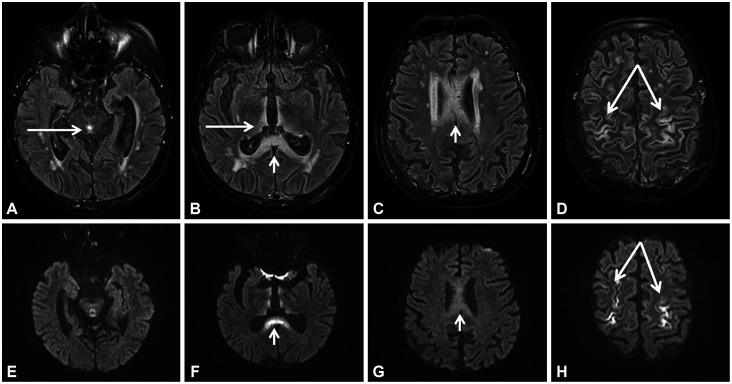

A Case of Cortical Involvement in Marchiafava-Bignami Disease Accompanying Wernicke's Encephalopathy.

J Clin Neurol. 2021 Jul;17(3):499-500. doi: 10.3988/jcn.2021.17.3.499.

A Case of Cortical Involvement in Marchiafava-Bignami Disease Accompanying Wernicke's Encephalopathy.一例伴有韦尼克脑病的马基亚法瓦-比尼亚米病皮质受累病例。